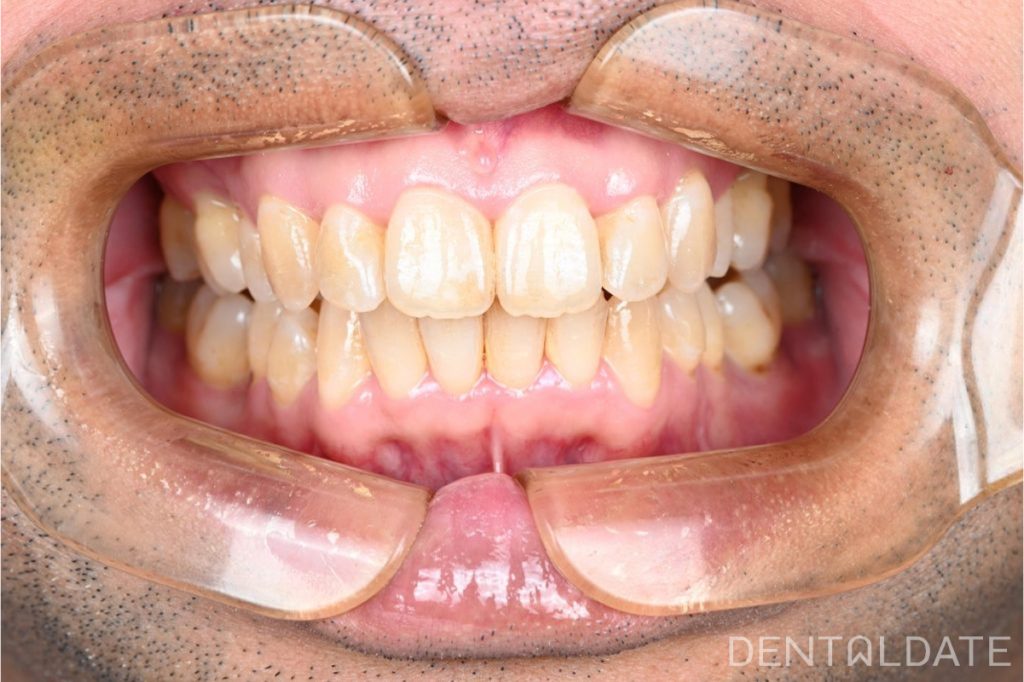

The patient, a programmer, sought treatment with complaints of pain in the shoulders, neck, and occipital region, along with significant discomfort while chewing, primarily on one side. Our diagnostic evaluation revealed uneven, imbalanced dental contacts, leading to muscle tension and postural issues.